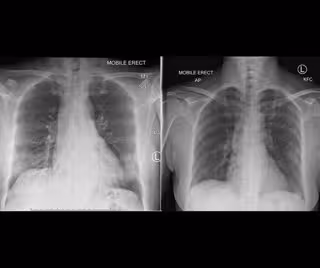

Investigadores del Instituto Peter Doherty para la Infección y la Inmunidad (Australia) han trazado un mapa de las respuestas inmunológicas de uno de los primeros pacientes con coronavirus de Australia, mostrando la capacidad del cuerpo para combatir el virus y recuperarse de la infección.

En su trabajo, publicado en la revista 'Nature Medicine', los científicos analizaron muestras de sangre en cuatro puntos temporales diferentes en una mujer sana de unos 40 años, que se infectó y tenía síntomas de leves a moderados que requerían ser atendida en el hospital.

El equipo pudo diseccionar la respuesta inmunológica que condujo a una recuperación satisfactoria del Covid-19, lo que podría ayudar a encontrar una vacuna eficaz. "Demostramos que, aunque la enfermedad está causada por un nuevo virus, en una persona por lo demás sana, una respuesta inmunológica robusta en diferentes tipos de células se asoció con la recuperación clínica de manera similar a lo que vemos en la gripe", detallan.